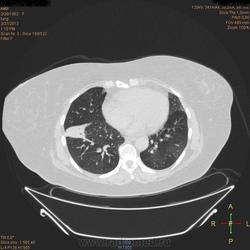

Здравствуйте, коллеги .Нужна помощь.Больная страдает Бронх.астмой.Беспокоять кашель,одышка , слабость, боль левой грудной клетке.Была температура 37,5- 38,0.Данный момент получает цефомизин темпер нормализовалось.Хочеть стационарное леч.Обратите пожалуиста на молочные железы, справа была операция год назад .Беспокоять боль правой мол.железе.

Во-первых, нет дайкомов. По представленным изображениям, изменения в левом легком дифференцировал бы между ТЭЛА мелких ветвей и организующей пневмонией, справа - пока вариантов нет (нужны дайкомы).

+1. Диф. диагностика между ОП и ТЭЛА обоих легких. Исключить ТЭЛА методом КТ с в/в боюсным контрастированием.